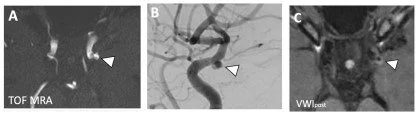

Vessel Wall MRI Added to MR Angiography in the Evaluation of Suspected Vasculopathies (July 2019)

3D-TOF-MRA and vessel wall MR imaging together identifies a higher number of abnormal vessel segments than 3D-TOF-MRA alone and may provide a more accurate assessment of disease burden.